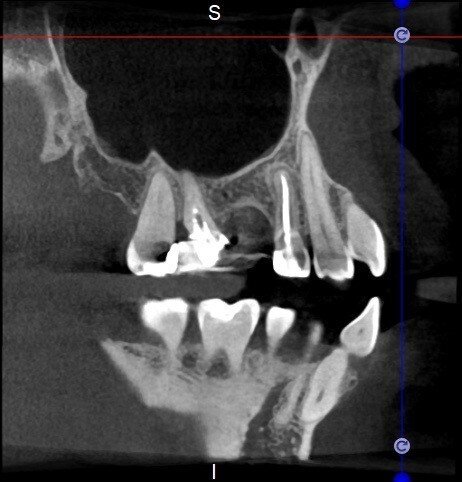

The case with which I would like to start my clinical review is a perfect example of how difficult it is to establish the origin of the patient’s symptoms on the basis of an intraoral radiograph alone. Not only does the 2D study fail to establish with certainty the presence of a lesion, but more importantly, it is impossible to establish the size, morphology and type of the lesion. An analysis of the 3D imaging, however, provides a clear picture of the clinical situation: the coronal and sagittal slices revealed the presence of a large lesion extending from the apex of the mesial root of this molar to the furcation, while the axial slices allow us to conduct a precise analysis of the endodontic anatomy and, in particular, the shape of the mesial root, which in this case was fused with the palatine root. A full overview of the case can, therefore, guide the decision-making process and direct the treatment plan towards a specific type of treatment (Figs. 1–4).